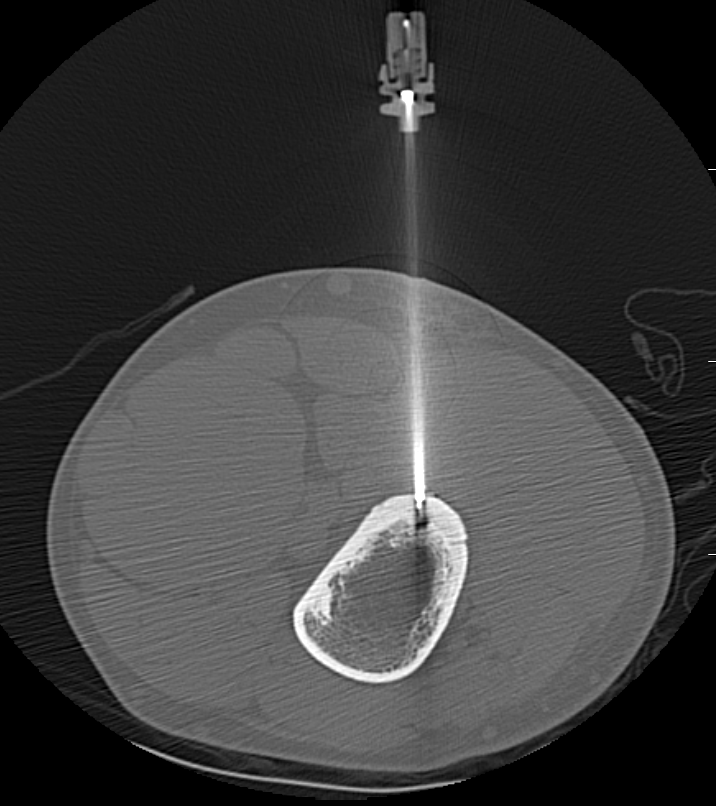

Technique

GA

- introduce electrode under CT

- tissue for histology

- radiofrequency

- increase temperature to 90o for 4 - 6 minutes